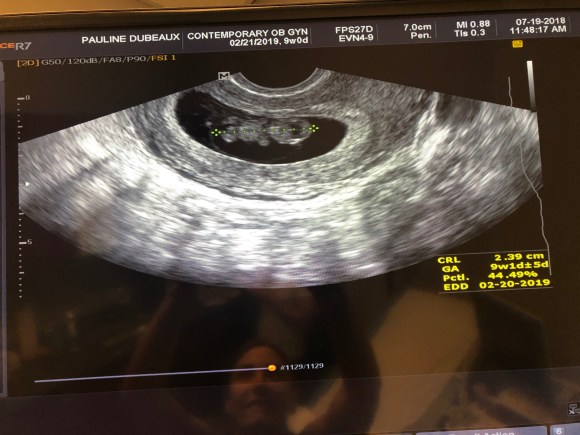

petit test s’est révélé positif! Il y a un petit être qui pousse et grandit en moi!